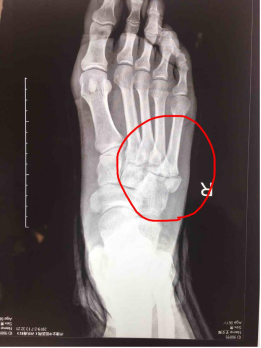

患儿,左足外伤,请帮忙确定第5跖骨是否骨折?

图1x线示第五跖骨近端骨骺增大,碎裂,骨与软骨交界处增宽(红色圈所指)